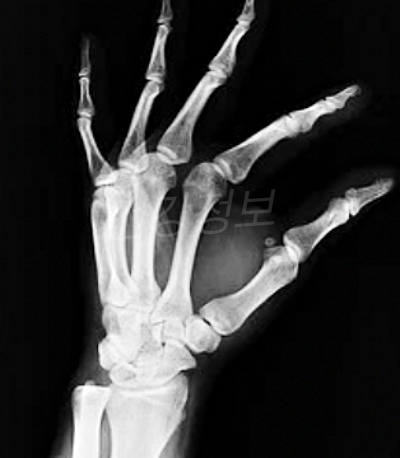

골다공증

골다공증이란 뼈 속에 있는 칼슘이 빠져 나가게 되면서 뼈의 밀도가 줄어드는 것을 말합니다. 사람은 나이가 들어감에 따라 성 호르몬이 줄어들면서 몸에서 점점 칼슘이 빠져 나가게 되죠. 또한 비타민 D 의 부족으로 인해서 골다공증이 생길 수도 있습니다.

우리 몸은 각 부위에 맞는 충분한 영양소가 흡수 되어야 하는데 그것들이 부족하게 되면 뼈의 구멍이 뚫리는 골다공증이 생길 수도 있는 것입니다.

골다공증이 생기면 당연히 뼈가 약해지고 그 사이로 바람이 스며들어 시린 증상과 뼈가 부러진은 증상들이 나타날 수 있습니다. 골다공증 예방을 위하여 어떤 음식이 좋은지 골다공증에 좋은 음식에 대해서 알아보겠습니다.